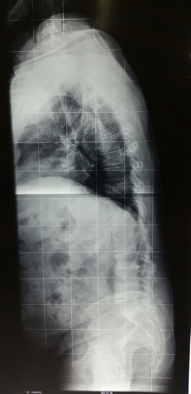

Observe este paciente com Escoliose Degenerativa com Flat/Back.

Ele apresente alteração do prumo tanto no plano sagital quanto no coronal decorrente de perda de altura discal e retificação da lordose lombar. Esta deformidade, comum em pacientes idosos, é grave e leva a perda na qualidade de vida e incapacidade funcional, por dor e fadiga muscular.

Neste exemplo o paciente apresenta importante deformidade no plano sagital com escoliose degenerativa compensada no plano coronal. A correção feita objetivou a correção das duas deformidades (plano sagital e coronal) e descompressão posterior.